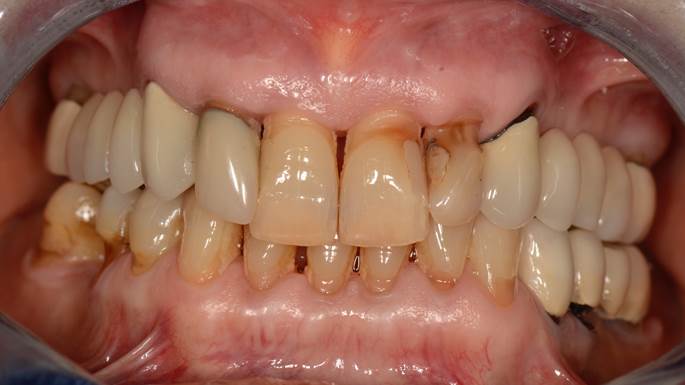

Clinical case: Full-mouth implants for mandibular & maxilla - restored using mixed prostheses

- Courtesy of Dr. Hyun Jun Kim, Korea -

Keywords

AnyRidge, full-mouth implants, mandibular, maxilla, edentulous, full mouth rehabilitation, Octa abutment, long-term clinical case, biological stability, Dr. Hyung Jun Kim